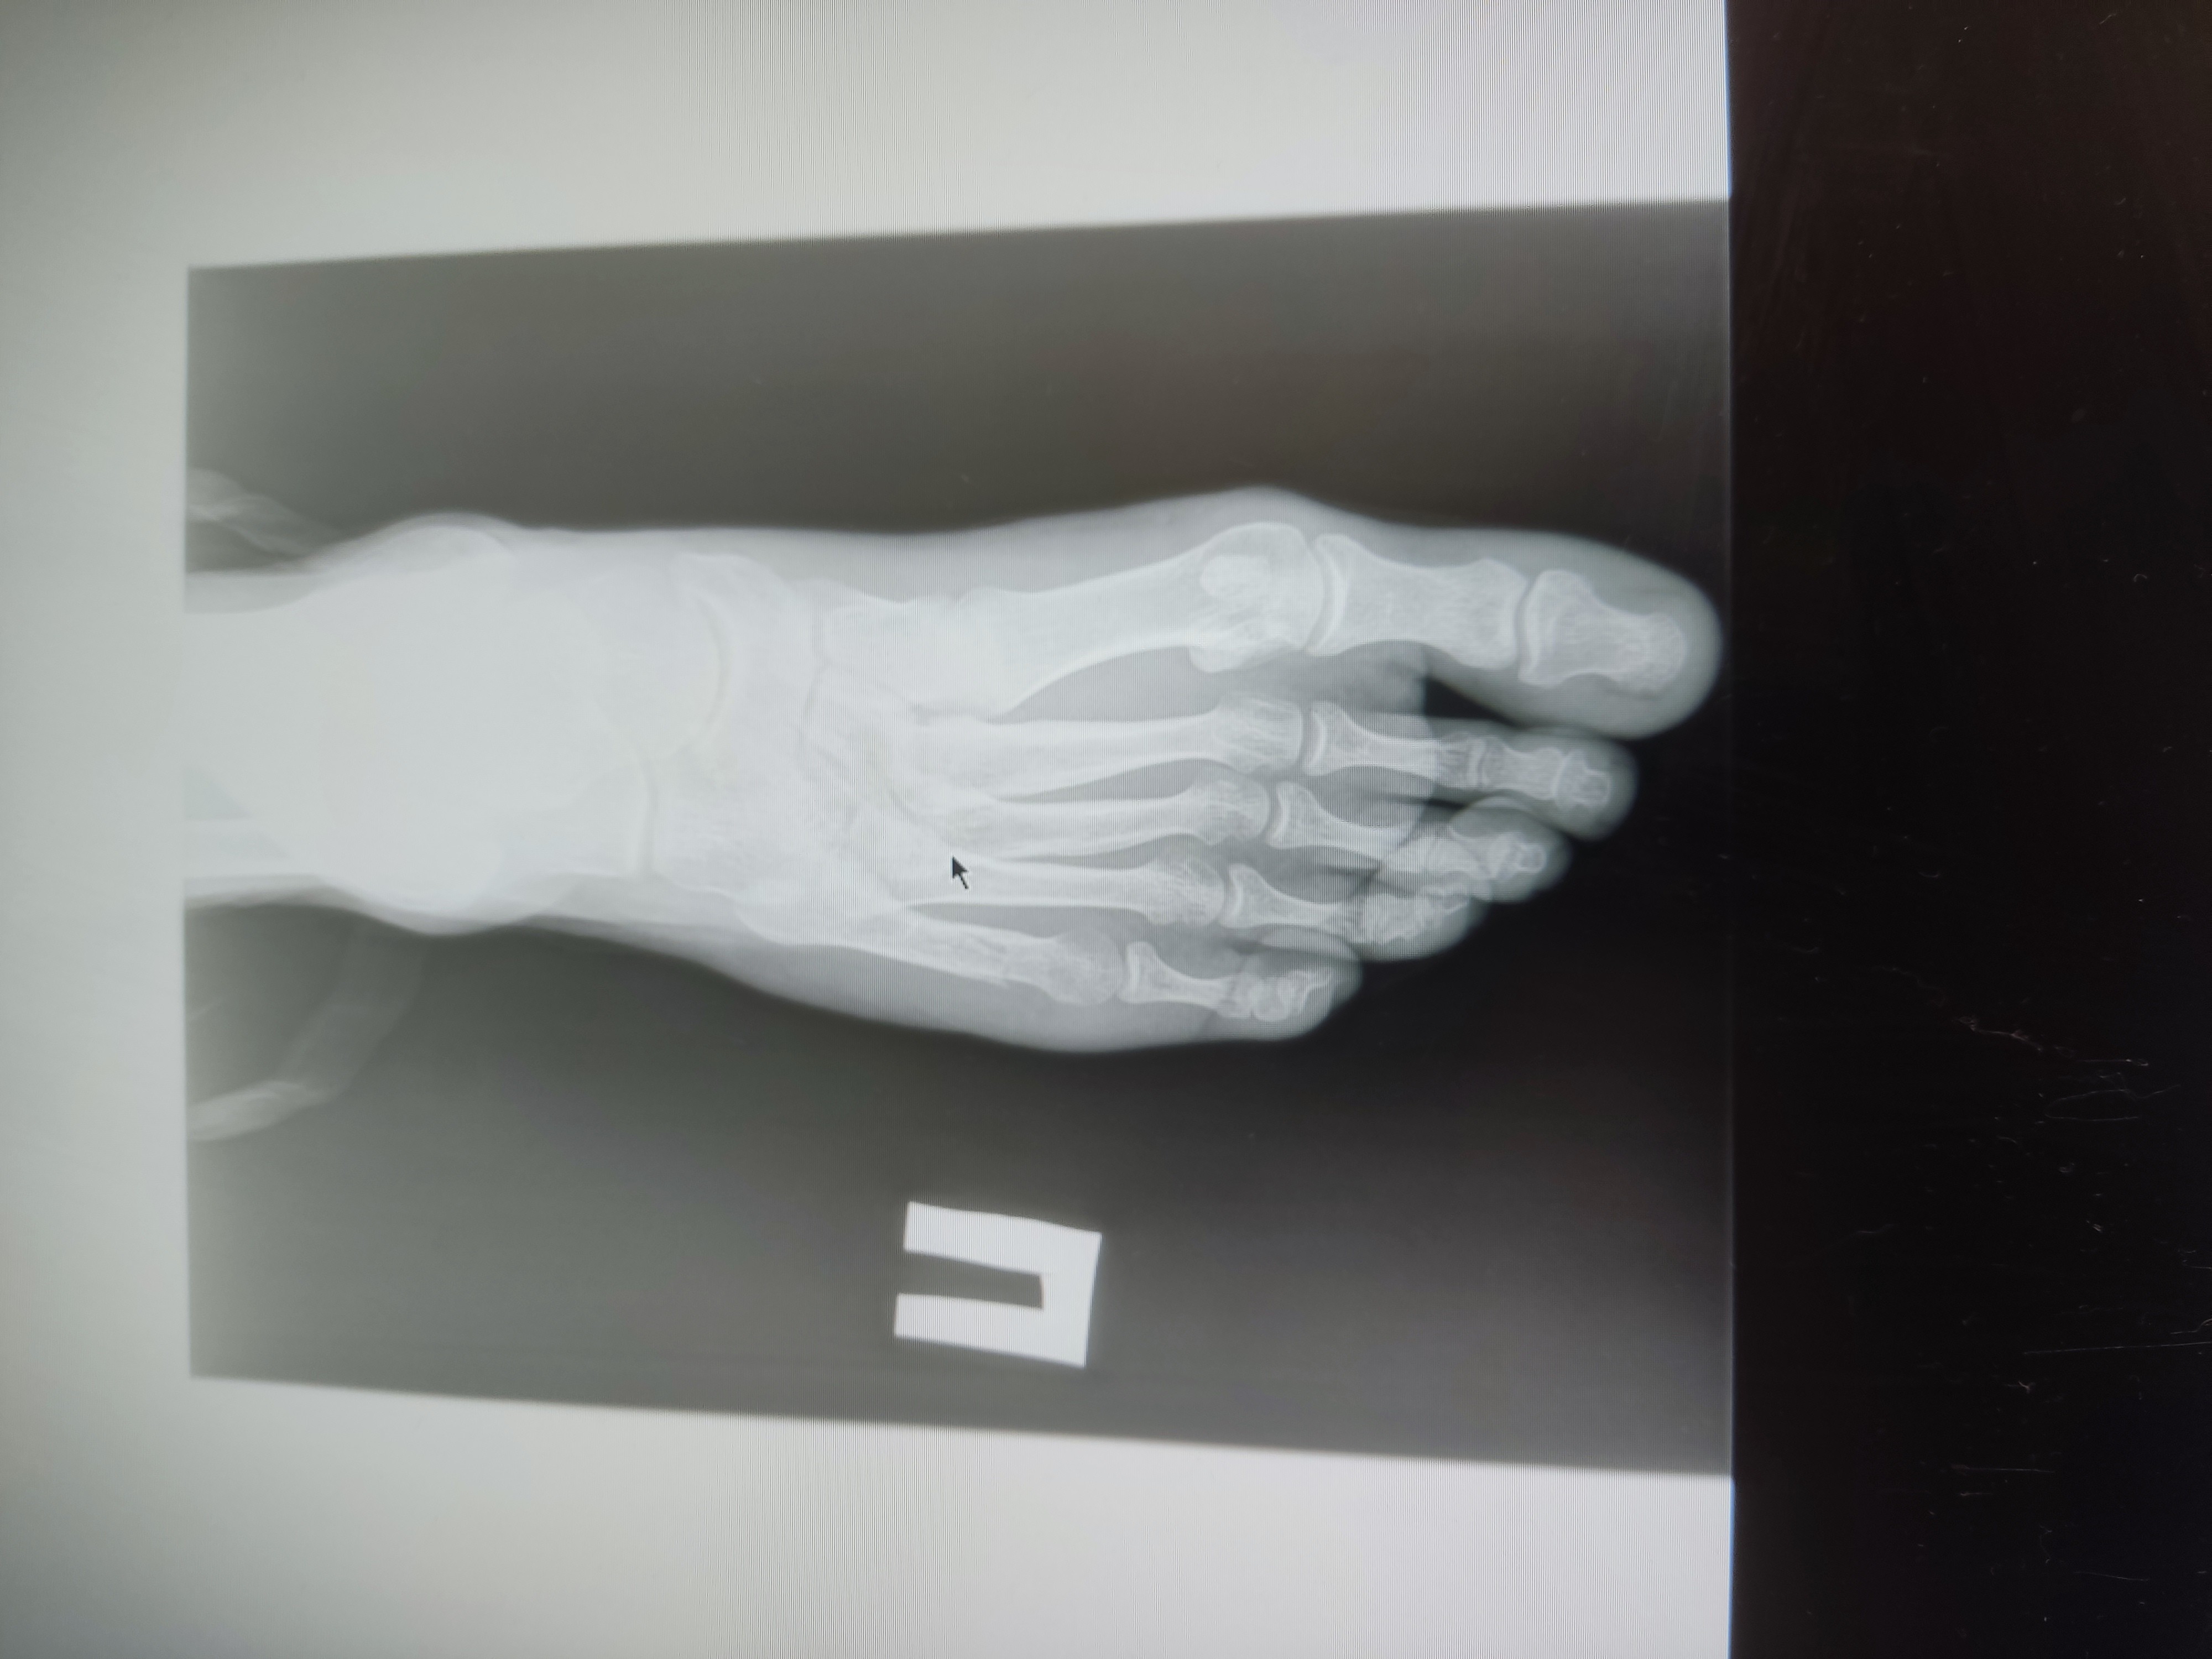

Анончики, не знаю в какой тред пойти, спрошу тут

На пикрил снимок спустя 14 дней после травмы.

Перелом пятой плюсневой со смешением 4мм, произошёл когда подвернул ногу, 32лвл

Гипс наложил на следующий день после травмы в травматологии травму получил в чужом городе.

Операцию не делали и ни один из двух травматологов моего и не моего города не говорил о её необходимости

Сейчас прошло 4 недели с травмы, местный врач сказала снимать гипс, врач другого города изначально говорил про 6 недель в гипсе. Назначили физио, скорее всего алмаг, точно узнаю на процедуре в понедельник

Основной вопрос — какова вероятность того, что я всю оставшуюся жизнь буду хромать?

4 недели должно срастись. вообще переломы 1 и 5 плюсневых костей оперируют, так как они опорные. пей витаминку Д и какой нибудь кальций (кальцемин или остеогенон). гипс снимать только после контрольного RG исследования. если есть признаки сращения, то снимать.

Аноним 05/12/25 Птн 07:28:10 1651121 138

1764908888974.jpeg 1478Кб, 4000x3000

4000x3000

1764908889204.jpeg 1052Кб, 4000x3000

>>1651107

Гипс сняли на 4 неделю писал прошлый пост без гипса уже, в день его снятия

Вчерашние снимки выглядят так, тут уже 5 недель с момента перелома

>переломы 1 и 5 плюсневых костей оперируют

Ну вот мне ни один из двух врачей не предлагал

>пей витаминку Д и какой нибудь кальций (кальцемин или остеогенон)

КальцД3 никомед и остеогенон начал пить на 3-4 день после перелома и пью до сих пор

Аноним 08/12/25 Пнд 21:43:13 1651610 139

>>1651121

мазоль уже образуется. не так быстро как хотелось бы, но все же. смещение умеренное. все будет хорошо.

Аноним 08/12/25 Пнд 22:00:04 1651615 140

1765220403918.jpeg 3838Кб, 4000x3000

>>1651610

Спасибо, анончик, обнадёжил

Последний снимок в прошлую пятницу назад по описанию показал 40% сращения, сказали, что можно неспеша ходить полноценно (а не с упором на пятку), продолжаю физио, назначили лфк и через две недели на работу. Со следующей недели начну передвигаться вне дома без трости

Итого 7 недель больничного будет. Видимо компенсация себе же за 7 лет без больничного

Полноценные длинные прогулки (от часа без перерыва) скорее всего буду вводить не раньше февраля (на третий месяц после перелома). Недавно гулял с тростью около получаса. Нога очень устала, в том числе передняя большеберцовая мышца. Мышцы за 5 недель ощутимо атрофировались, по всей видимости

Банально отвык ходить видать